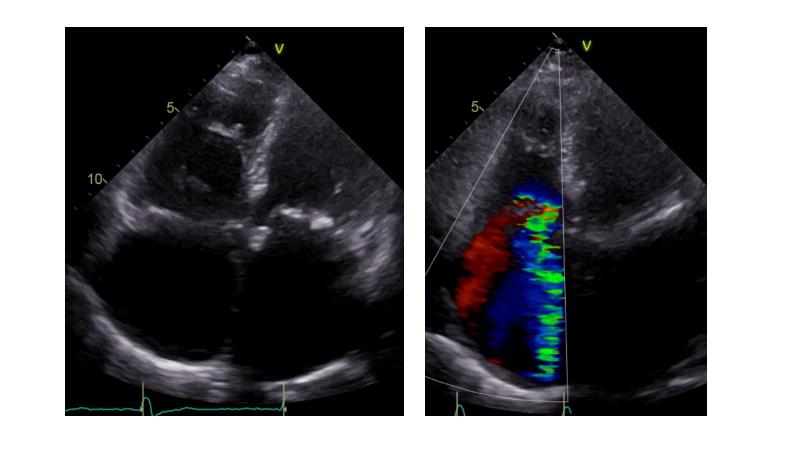

Based on an in-depth review of the data from TRILUMINATE pivotal, a randomized trial whose findings were recently published in the NEW ENGLAND JOURNAL of MEDICINE, this lecture explains how these results will impact clinical practice in the treatment of tricuspid regurgitation. Join the speakers and learn more.

- To understand why it is key to intervene in tricuspid regurgitation disease - A safe option for an unmet need

- To learn how TRILUMINATE Pivotal - the first randomised trial - is impacting the clinical practice in tricuspid regurgitation treatment

- To understand how the broadest body of evidence supports TriClip therapy as first line treatment option for tricuspid regurgitation